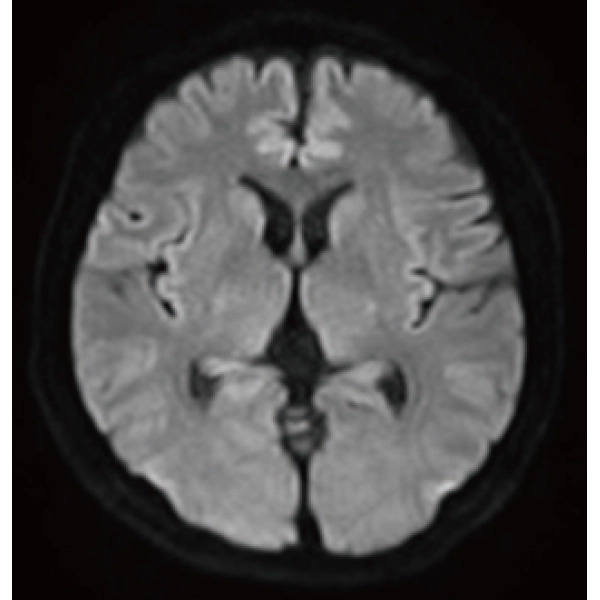

"DLR" is applicable to all body parts and promotes high speed imaging and diagnostic efficiency

IP-RAPID x DLR Plus can also shorten imaging time, allowing more images to be taken in the same examination time.

Additional imaging, such as different image types and cross sections, can be added to the conventional examination to increase the amount of information and make the diagnosis more reliable.

IP-RAPID x DLR Plus can be used for basic imaging such as VolumeScan, RadialScan, HalfScan, and many other imaging methods such as MultiContrastScan FatSep and DWI.

It can also be used with time-consuming scans such as Whole Body DWI and Whole Spine imaging, providing more detailed information in many areas than previously possible.